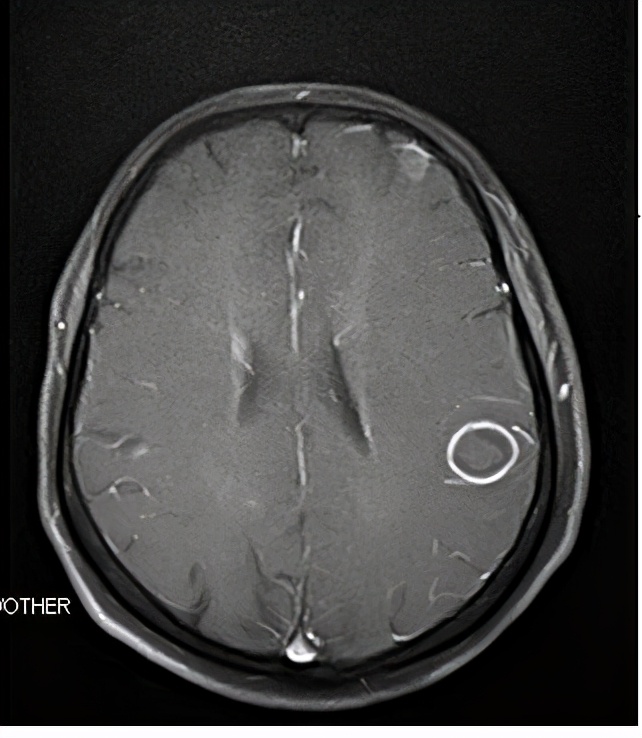

改变治疗方案后脑转移明显缓解(磁共振)